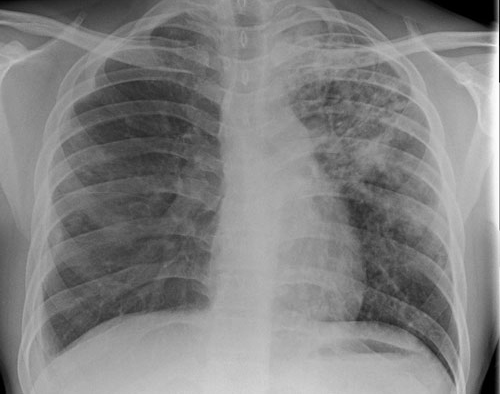

For suspected pulmonary disease the initial clinical assessment has not changed in decades, with chest radiography and the collection of three deep respiratory samples for smear microscopy and culture remaining the standard of care, see figure 1.

Despite developments in novel diagnostics it is important to bear in mind that sputum samples and chest radiography remain the mainstay of diagnosis for suspected active pulmonary disease.